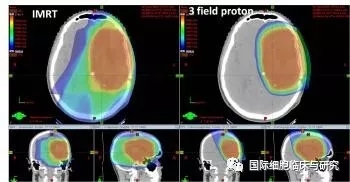

质子治疗是一种比其他任何形式的放射治疗更准确,更精确地靶向肿瘤,同时保留健康组织,目前全球最先进的一种放疗技术。通过质子治疗,可以完全避免靶标外部的绝大多数不必要的辐射。

与传统形式的辐射相比,质子束会到达肿瘤内部的精准位置而不是沿着光束离开人体的路径释放大部分辐射剂量。实际上,质子没有肿瘤之外的辐射“退出剂量”,这意味着质子停在肿瘤上,不会继续伤害身体的健康部位。

专家们认为大多数儿童中枢神经系统肿瘤、颅底肿瘤和视网膜母细胞瘤都适合接受质子治疗。为了进一步探讨不同位置的肿瘤是否适合接受质子治疗,专家们对室管膜瘤、颅咽管瘤、髓母细胞瘤和横纹肌肉瘤的光子和质子治疗计划进行了对照。

所有的治疗计划对照结果都显示,质子治疗的总剂量更低,尽管这对治疗结果的影响有多大仍然有争议。